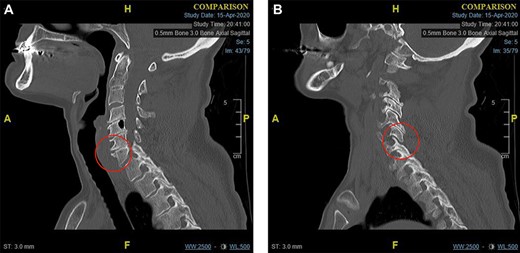

The left shoulder radiograph showed no abnormality. The sagittal images of the cervical spine CT scan are shown in Figs 1 and 2a and b. Figure 1 is the mid-sagittal slice of the CT scan at presentation and shows no obvious malalignment.

Midline sagittal CT scan of the cervical at the time of first presentation.

(a) Para-midline sagittal CT scan of the cervical spine at the time of first presentation showing a fracture of the antero-superior osteophyte of C7 (indicated with a circle). and (b) Para-midline sagittal CT scan of the cervical spine at the time of first presentation showing opening of the C6/C7 facet joint (indicated with a circle).